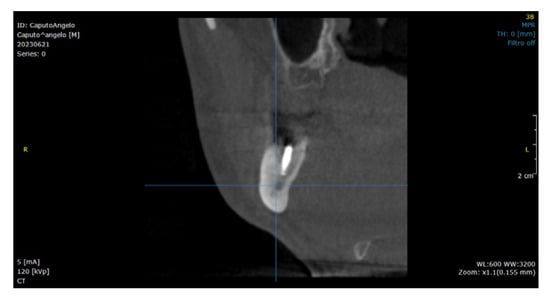

2.2. Surgical Technique

3. Results